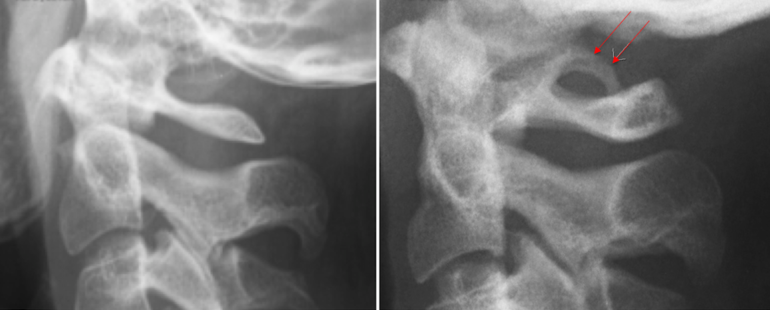

Неврологи различают 2 вида синдрома. В первом случае появляется костная дужка, которая соединяет суставной отросток атланта и его заднюю дугу. Во втором аномалия представлена в виде костной дужки, расположенной между суставным и поперечным отростками. Патология любой формы имеет одно- или двухсторонний характер.

Также неврологи классифицируют аномалию Киммерли на 2 формы — полную и неполную. При полной дужка представлена в виде полукольца, а при неполной возникает дугообразный вырост справа либо слева от позвонка.

Для постановки диагноза назначается рентгенография черепа и шейного отдела. Аномалия Киммерли чётко видна на рентгенограмме при обследовании краниовертебрального перехода. Если пациент жалуется на ушной шум, чтобы исключить лор-болезнь, требуется консультация отоларинголога. Проводится аудиометрия, при необходимости назначаются дополнительные методы исследования слуха.